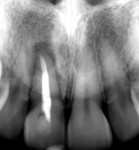

In a representative case, a 32-year-old female patient presented with a failing maxillary central incisor (tooth No. 8) (Figure 2 and Figure 3). Clinical evaluation showed harmonious gingival architecture and good oral hygiene. Radiographic examination, including periapical radiographs and CBCT, indicated periapical radiolucency and absence of facial bone around the failing tooth No. 8 (Figure 4 and Figure 5). Further examination through bone sounding on the facial aspect of tooth No. 8 revealed a U-shaped bone wall defect (Figure 6 through Figure 8). After treatment options were presented, the patient elected to replace the failing tooth No. 8 with IIPP in conjunction with C-BG and C-CTG.

Case Presentation: Definitive Prosthetic Phase